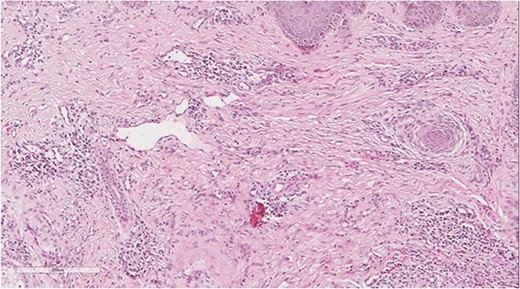

A 5 mm skin punch biopsy was also taken from the neck. Histopathology showed cystically dilated hair follicle with surrounding fibrosis and heavy inflammatory infiltrate and granulation tissue (Fig. 1), the inflammatory infiltrate is composed of lymphocytes, plasma cells, neutrophils and histiocytes (Fig. 2). The overall morphologic picture was suggestive of follicular occlusion syndrome (Fig. 3). A diagnosis of HS was made, and the patient was started on rifampin 600 mg OD and clindamycin 300 mg BID. A lipid panel was ordered as well and showed a triglyceride level of 1.99 mmol/L (0.7–1.7 mmol/L).

Perivascular lymphoplasmacytic infiltrate that is a common finding in HS.